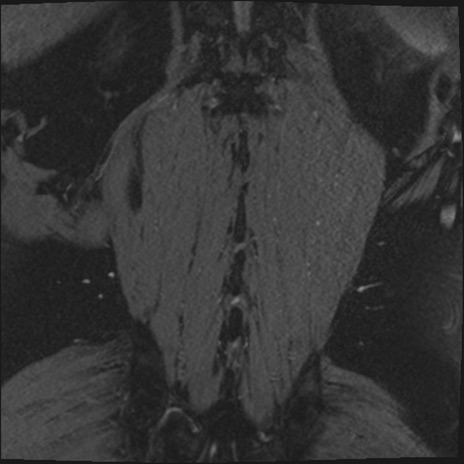

【整形】TIPS症例2 腰椎MRI 3D(冠状断像)

【症例】70歳代男性

【主訴】左下肢痛

【現病歴】2週間前くらいから腰痛、左下肢痛あり。左臀部から大腿、下腿外側のしびれが常時ある。歩行とともに同部位の痛みあり。

【身体所見】Lasegue70-/60+、Bragard-/±、PTR ±/±、ATR -/-、IP 5/5、TA 5/4、TS 5/5、EHL 右第1足趾なし/3、FHL 5/5、hypersthesia(-)、足背動脈触知良好

異常所見と診断は?